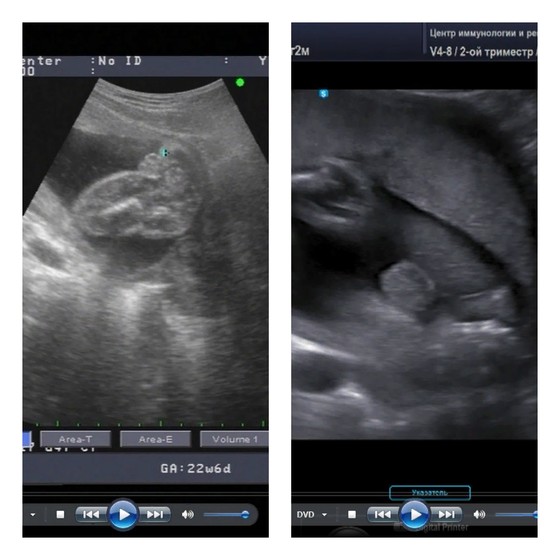

На левом стопкадре с видео - дочка, на правом - малыш, которого сейчас ношу (последнее УЗИ; делала опытный специалист в ЦИР; писюн в кадр не попал почему-то - сказали прижат к мошонке выше, но я так его и не разглядела). Оба между ножек.

На первом девочка, моя дочь, которой сейчас 6 лет)) смотреть там, где маленький синий крестик.